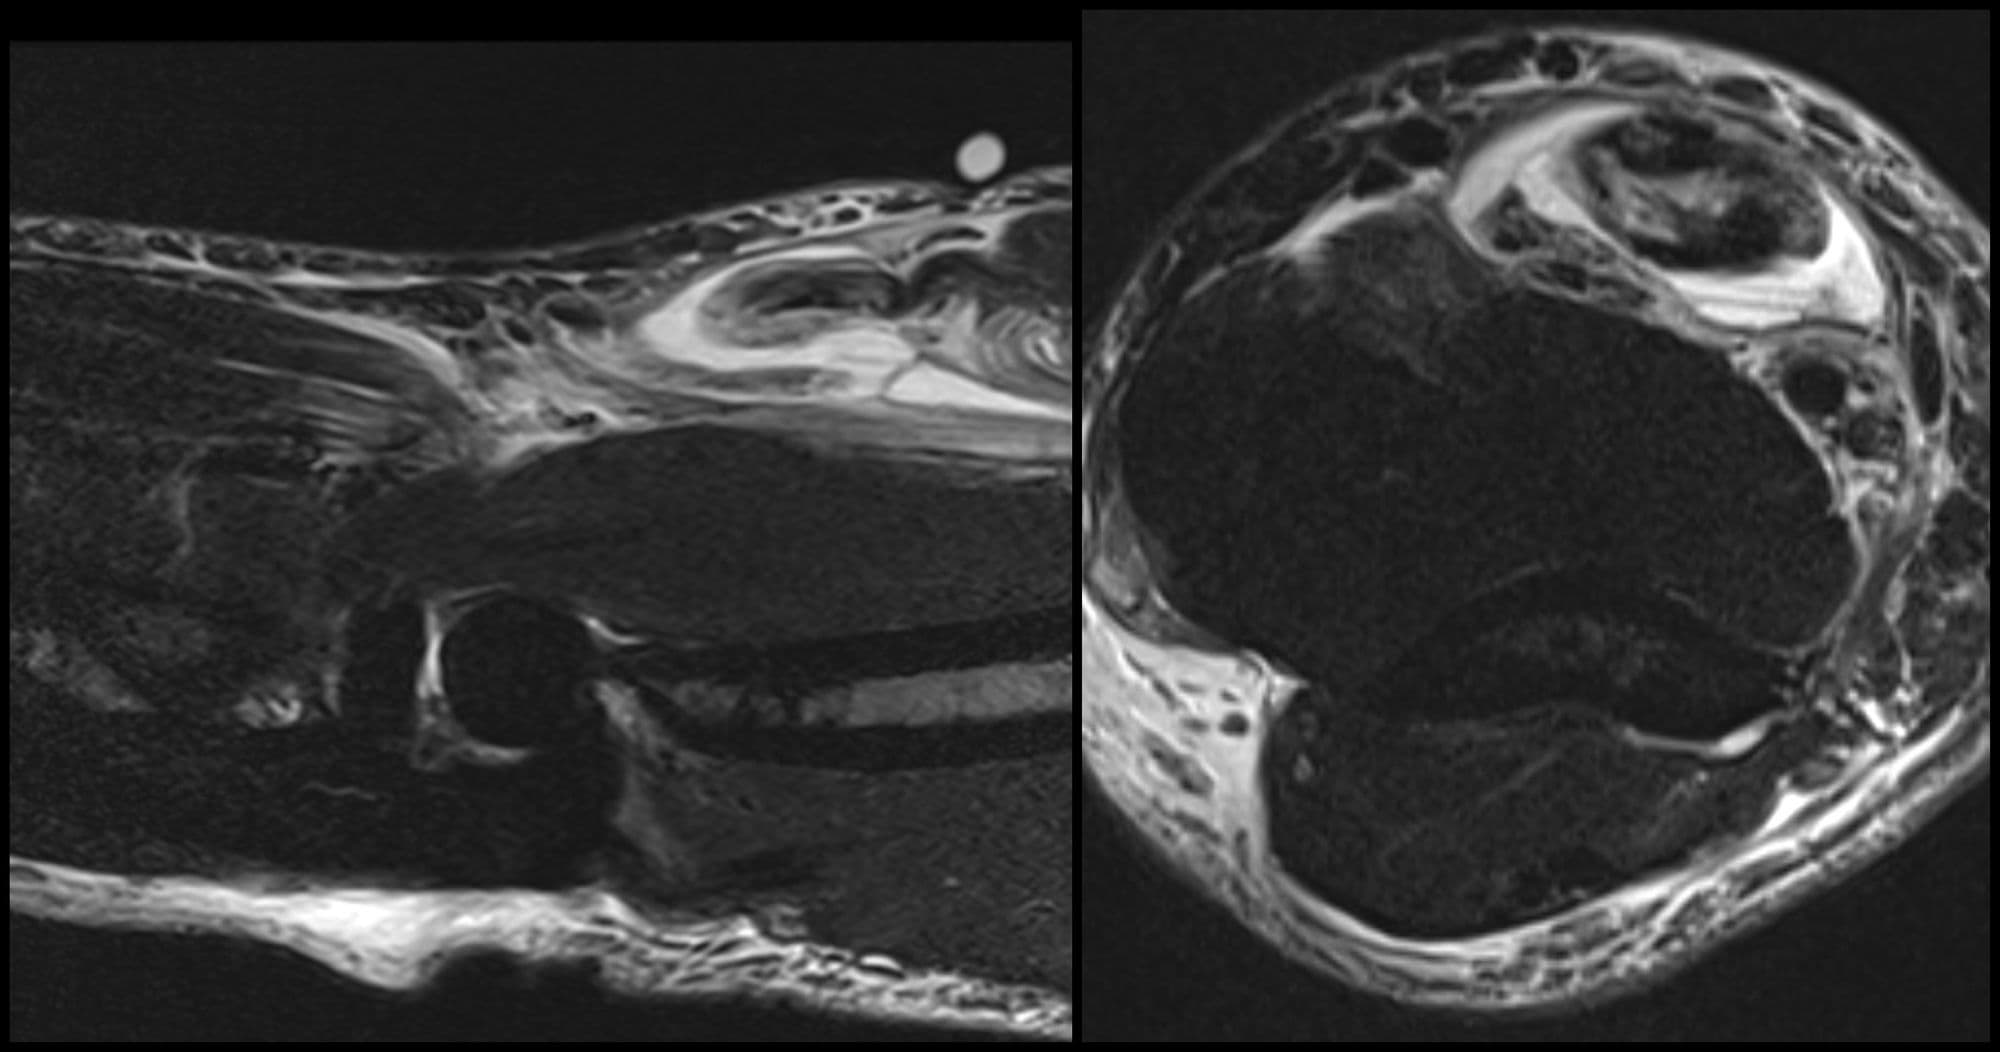

ACL Reconstruction (BTB autograft)